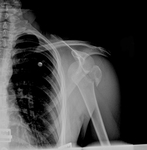

Anteroposterior x-ray view of a shoulder showing an anteroinferior dislocation

Personal collection of Dr Paul Novakovich